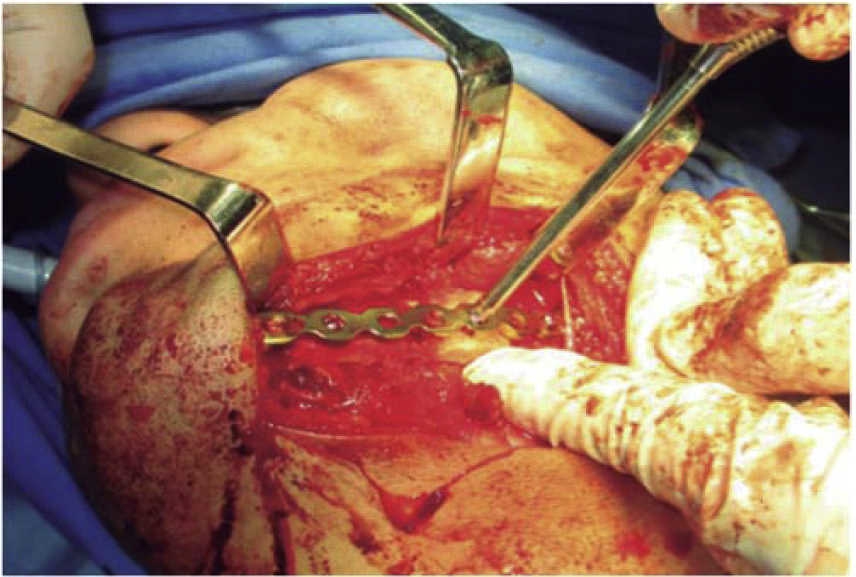

The second surgical event took place seven days later, performing extraoral approach. The fracture was reduced and bone edges were fixated with a 2.4 precontoured mandibular reconstruction plate (Figure 6). Occlusal stability was verified before suturing tissues and bar arches were removed (Figure 7). The patient remained in hospital for seven days, after which he showed suitable occlusion and appropriate healing. Suture points were then removed, a control study was performed and the patient was discharged. The patient did not attend control visits due to the fact that he was incarcerated.

Treatment was initiated with immunization, antibiotic therapy, analgesia, extraction of septic foci and mechanical cleansing of the wound. The patient lacked removable or partial prostheses, so in order to establish inter-maxillary relationship and facial height, gunning splints were manufactured in order to establish inter-maxillary relationship (Figure 13). After ten days of initial treatment, the patient exhibited suitable alveolar healing, with presence of non-fetid secretion at the level of the mandibular wound. The second procedure was then undertaken with extra-oral approach; a 2.4 mandibular reconstruction plate and a 2.0 bone segment plate were used (Figures 14 and 15). The patient was discharged, and she attended periodic assessment visits which showed suitable healing (Figure 16) and adequate mandibular mobility. Three weeks after reconstruction, the patient was instructed to initiate prosthetic treatment in order to achieve rehabilitation.